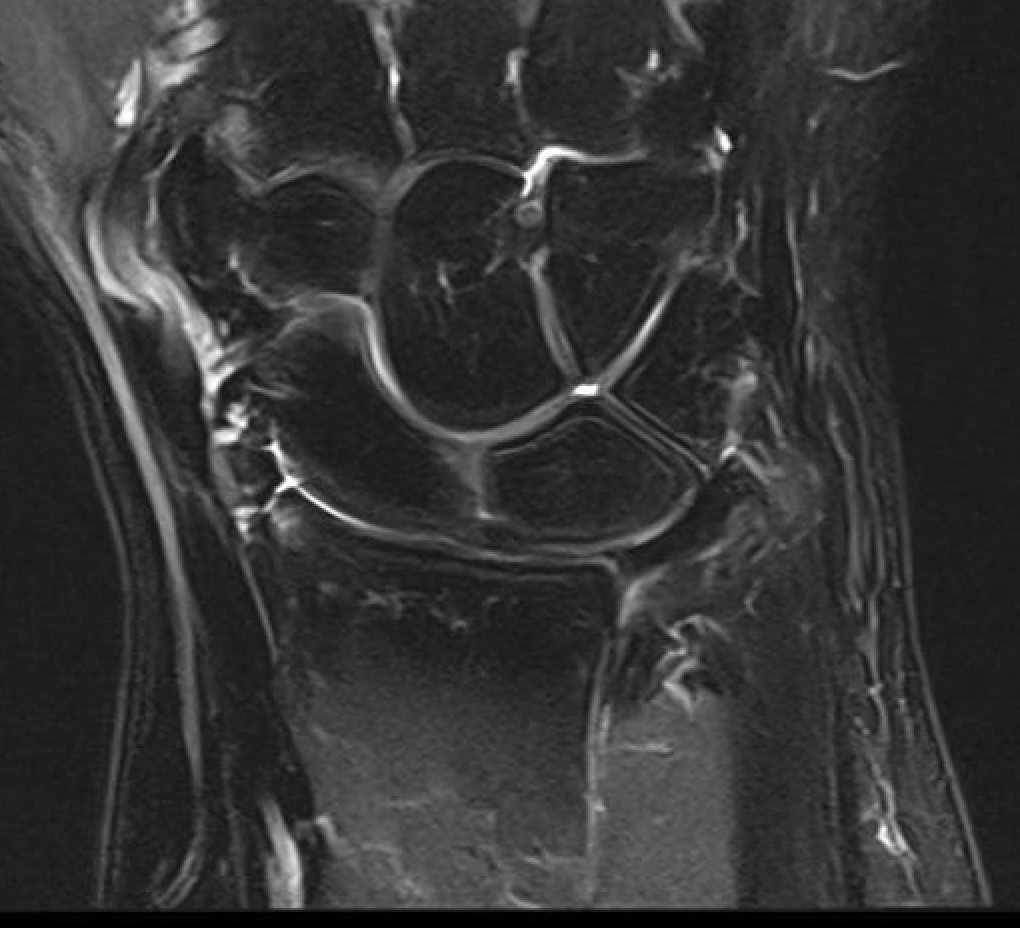

MRI

Normal

TFCC tears

Ulna sided tear

Radial sided TFCC tear

Central TFCC tear

Ulno-carpal abutment